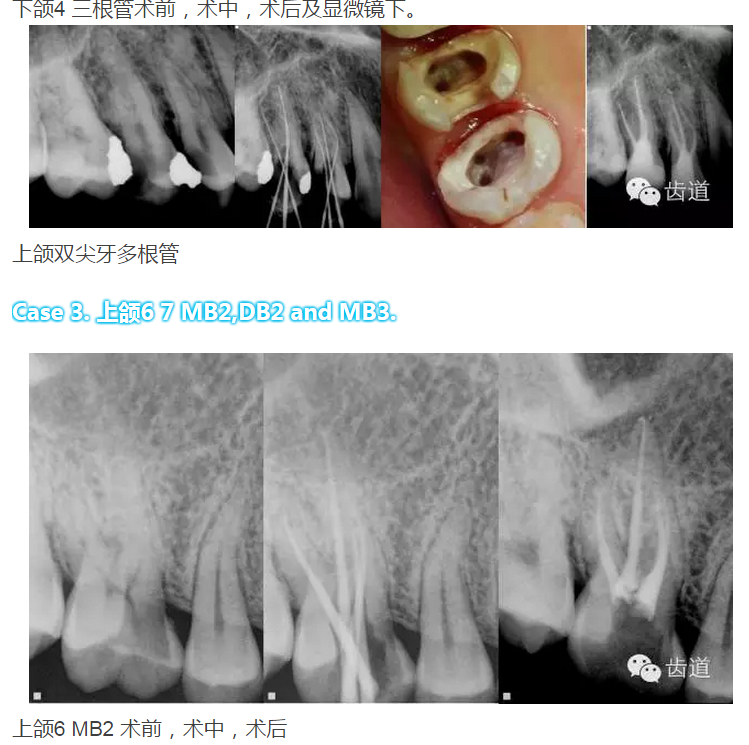

下頜第一前磨牙:多為單根管,少數(shù)為雙根管,三根管發(fā)生率為 0.46-0.5%,側(cè)支根管發(fā)生率44.3%;

下頜第二前磨牙:多為單根管;

上頜第一前磨牙:87%為雙根管,其次為單根管,另有2.4%為三根管,側(cè)支根管發(fā)生率49.5%;

上頜第二前磨牙:75%為單根管,其次為雙根管,側(cè)支根管發(fā)生率59.5%;